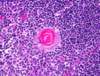

מה מסומן במס 2 בתמונה?

Germinal center

Lhymph nodule בתוך ה

מסומן במס 2 בתמונה

המוקד בו לימפוציטים מסוג B

מתחילים את תהליך הדיפרנציאציה והפרוליפרציה שלהם

Lympth nodule איך קוראים למרכז הבהיר ב

Germinal center

מסומן במס 2 בתמונה

המוקד בו לימפוציטים מסוג B

מתחילים את תהליך הדיפרנציאציה והפרוליפרציה שלהם

Germinal center מהו

מסומן במס 2 בתמונה

Lympth nodule המרכז הבהיר ב

המוקד בו לימפוציטים מסוג B

מתחילים את תהליך הדיפרנציאציה והפרוליפרציה שלהם

איך קוראים למבנה ההסטולוגי המסומן במס 3?

Corona

Germinal center מסביב ל

(CAP אם האיזור לא יקיף את כל הזקיק הוא ייקרא)

Corona מהו המבנה ההיסטולוגי ?

מבנה ההסטולוגי המסומן במס 3

Germinal center מסביב ל

(CAP אם האיזור לא יקיף את כל הזקיק הוא ייקרא)

מה בתמונה?

lymphatic node

קשר לימפה